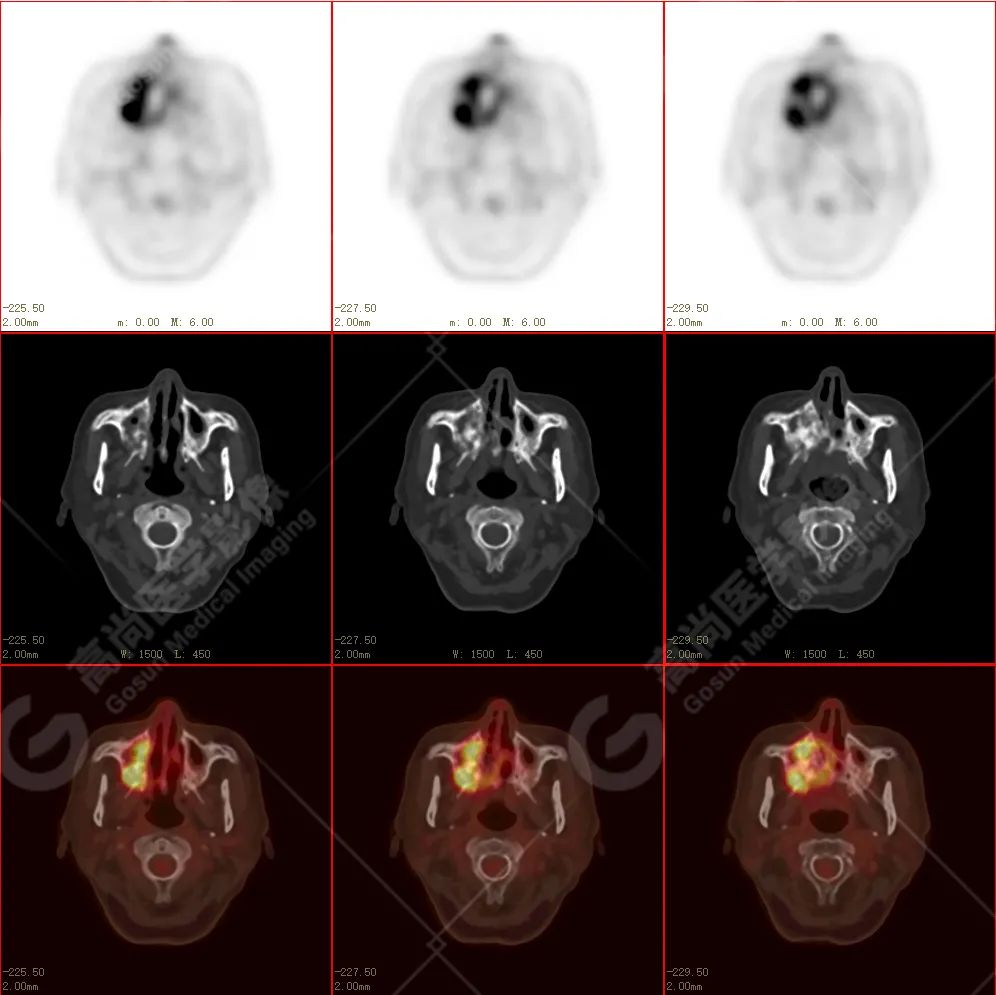

右侧上颌骨-上颌窦骨壁-骨性鼻中隔区域见片块状放射性摄取异常增高影,最大层面约 4.1 cm×3.8 cm×2.8 cm,SUV 最大值为 10.4,CT 示上述部位见成骨性改变,骨质不均匀弥漫性增厚、密度不均匀增高,并可见肿瘤骨影,边缘毛糙,周围伴软组织增厚。

根治性手术在放疗后骨肉瘤的治疗中是必须的,然而根治性手术仅仅适用于早期的病例,如本例病人,相对早期,周围组织结构无明显侵犯,PET 示肿瘤代谢也局限于肿瘤本体。